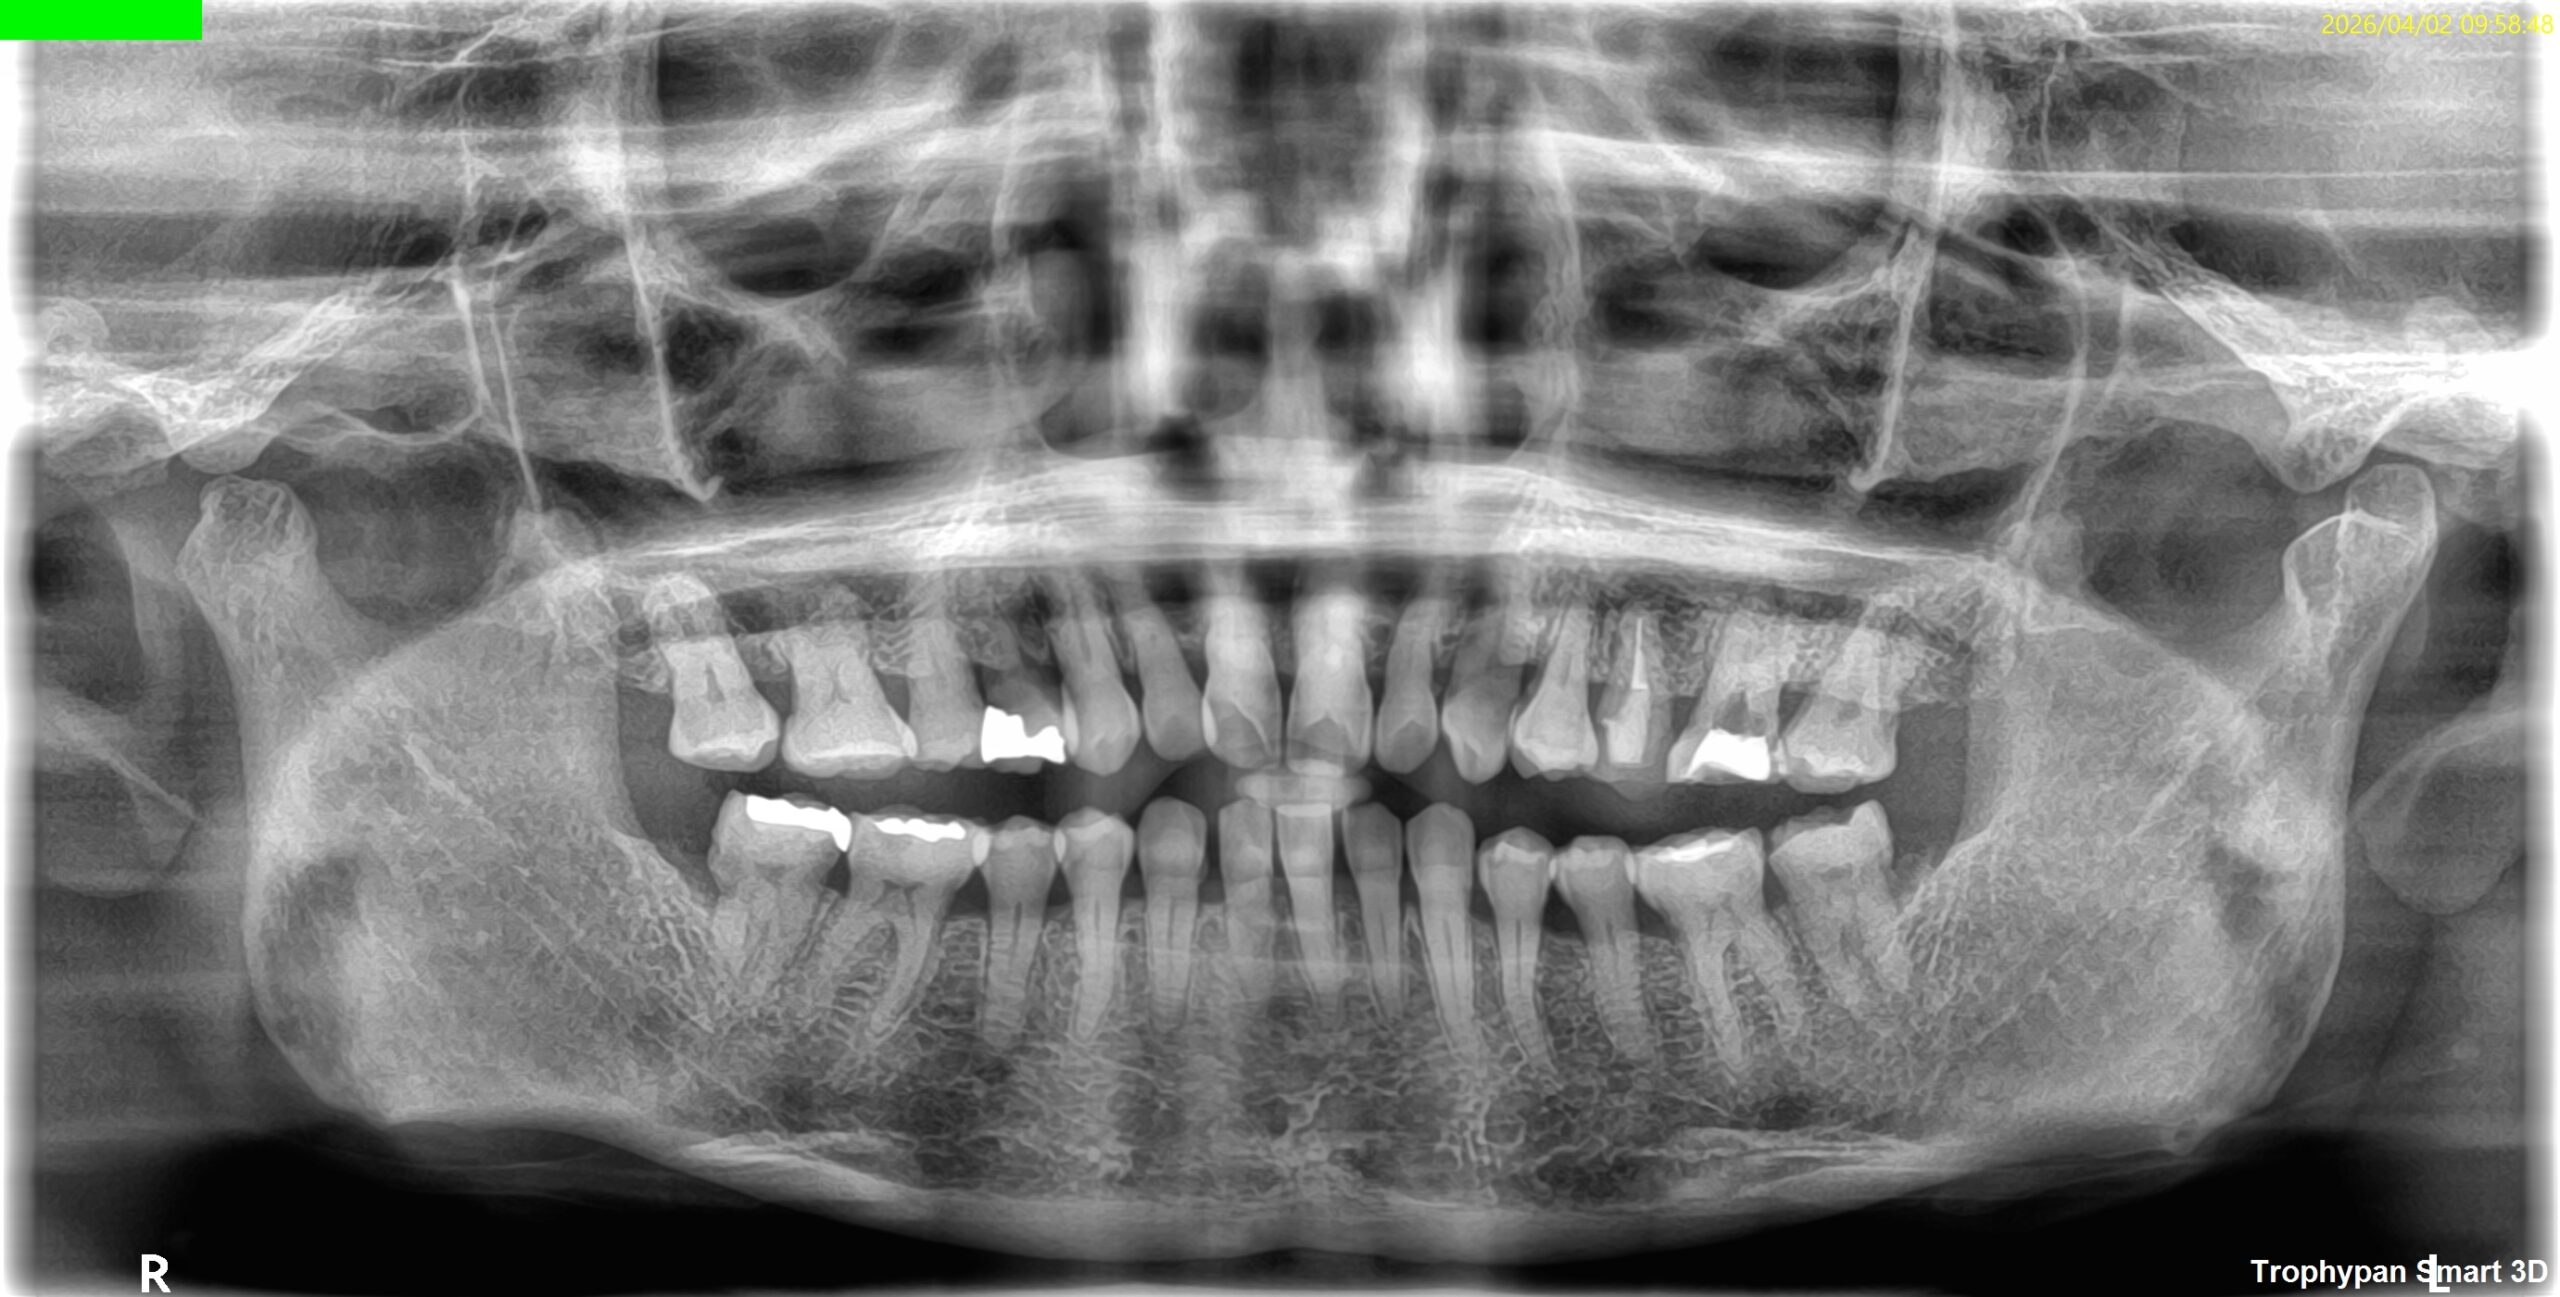

患者さんにいただいたレントゲンは以下である。

画質の悪いパノラマ写真だ。

これで根管の何を判断できるというのだろうか?

私には皆目見当がつかない。